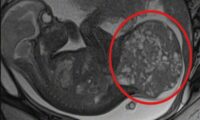

“L’eccezionalità di questo traguardo è legata a diversi fattori: il 15-20 % dei bambini con sindrome dell’intestino corto (SBS) è destinato alla nutrizione parenterale per il resto della sua vita e una percentuale intorno al 10-15% di essi va incontro a decesso a causa delle complicanze di questa tecnica. Inoltre le terapie considerate recentemente come “definitive” di questa sindrome e cioè il trapianto di intestino e la chirurgia viscerale (non trapiantologica) di allungamento di intestino non hanno portato ai risultati attesi, rispettivamente per l’alta mortalità e l’inefficacia”, spiega il gastroenterologo del Gaslini Paolo Gandullia.

“Il trattamento con il farmaco teduglutide, analogo del GLP2, permette la crescita dell’intestino in tutte le sue parti e funzioni con possibilità di svezzamento dalla nutrizione parenterale o di riduzione dei giorni di trattamento parenterale nei casi selezionati di sindrome dell’intestino corto, in cui la nutrizione parenterale non trova alternative di trattamento. Un traguardo raggiunto grazie alla sinergia tra clinica e ricerca d’eccellenza, che adempie pienamente alla mission del nostro ospedale pediatrico” conclude il dottor Gandullia.